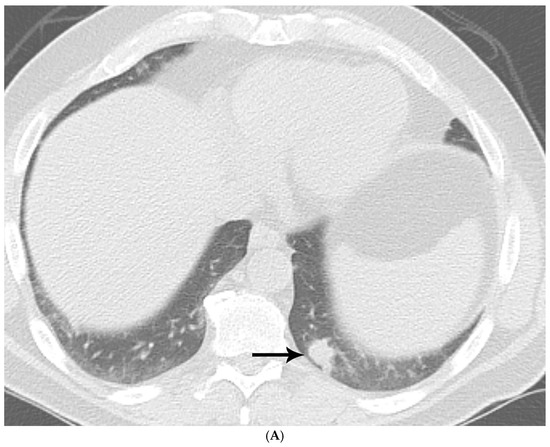

Histoplasma spp.: Lesions appeared to have well-circumscribed borders, less cellularity, peripheral calcifications in some cases, and central necrosis. GMS histochemical stains showed the presence of numerous small budding yeasts organisms (Figure 1A–D).

Figure 1.

(A) CT shows a left lower lobe well-circumscribed 2 cm solid nodule (arrow); (B) PET/CT shows that the nodule (arrow) is FDG avid with a standard uptake value of five, suspicious for lung malignancy; (C) well-circumscribed necrotic nodule with focal areas of calcification; and (D) GMS stain showing numerous budding yeasts of Histoplasma.